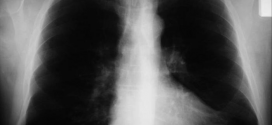

FIBROSIS PULMONAR IDIÓPATICA (FPI)

La fibrosis pulmonar idiopática (FPI) o (EPID). También llamada fibrosis pulmonar primitiva. Resumiendo: La fibrosis pulmonar idiopática (FPI) es una enfermedad debilitante, caracterizada por una progresiva cicatrización de los pulmones, que dificulta cada vez más la respiración. La FPI pertenece a una familia de aproximadamente 200 enfermedades relacionadas, denominadas enfermedades pulmonares intersticiales (EPI), que tienen características similares y pueden ocasionar …